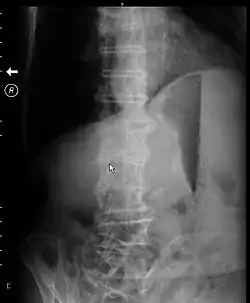

![]() تم التقاط الأشعة السينية من البطن لشخص يعاني من انسداد في مخرج المعدة أثناء على جانبهم. هناك فقاعة هواء معدية بارزة ، ومستوى سائل هواء معدي ، و معدة متوسعة مع جسيمات بداخلها. تم التقاط الأشعة السينية من البطن لشخص يعاني من انسداد في مخرج المعدة أثناء على جانبهم. هناك فقاعة هواء معدية بارزة ، ومستوى سائل هواء معدي ، و معدة متوسعة مع جسيمات بداخلها. | |

قد تظهر الأشعة السينية للبطن مستوى سائل في المعدة مما يدعم التشخيص.